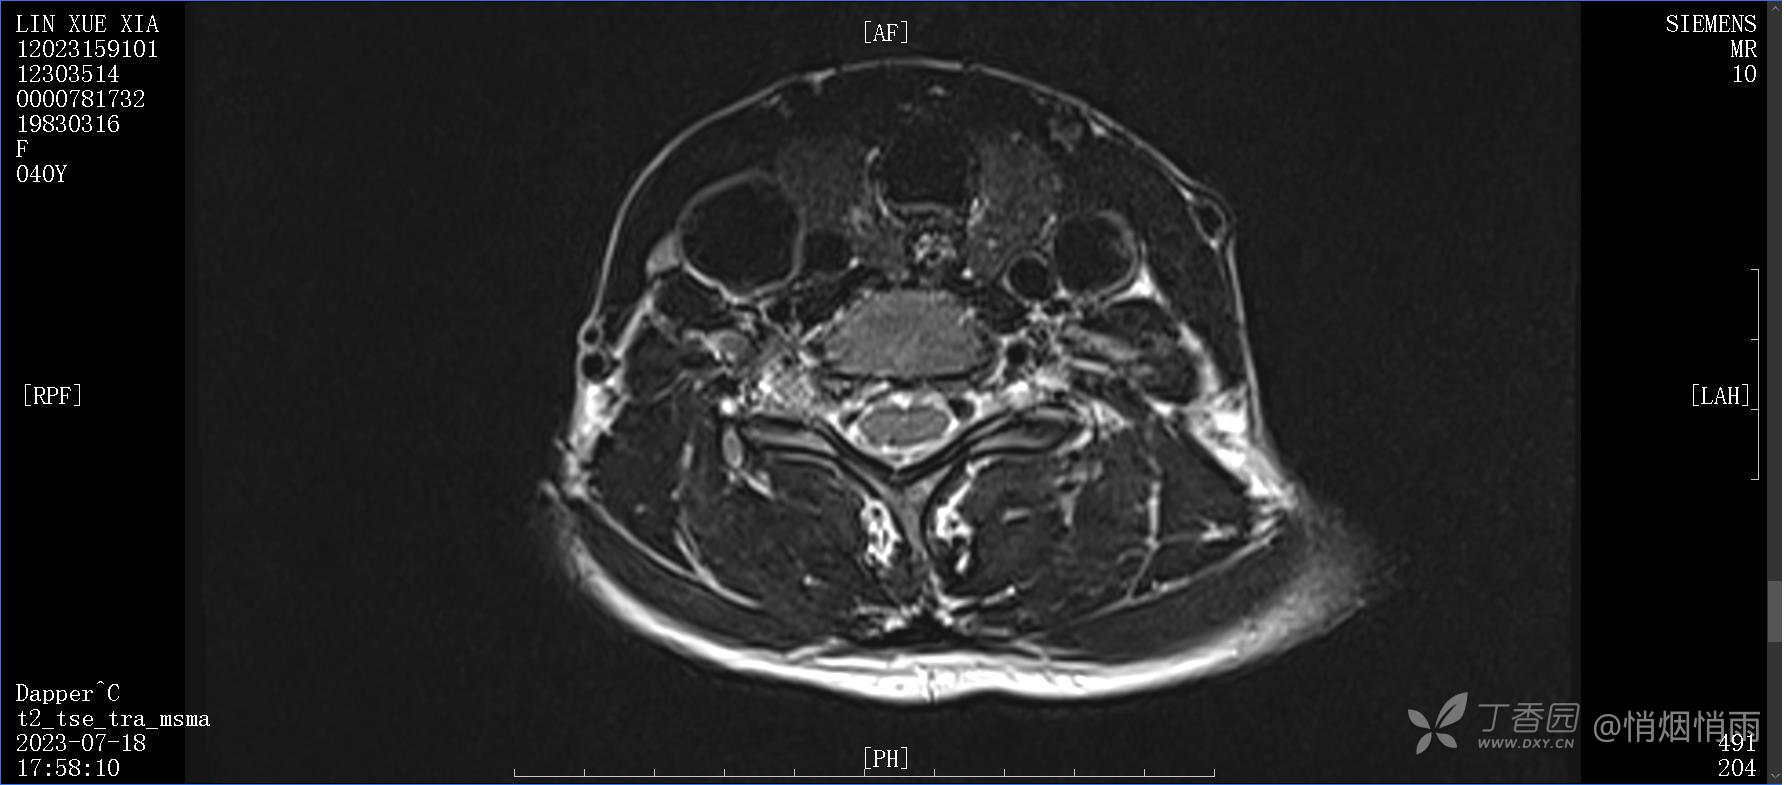

查体:右肩关节局部轻度肿胀,肩胛区压痛明显,痛处不固定,肩关节痛性活动受限,jobe test(+),lift -off test(+),中指、环指感觉较余指减退,余肢端感觉及血运情况可。

目前的诊断,暂时依据辅助检查诊为肩袖损伤,但是患者疼痛的性质和特点,却不是单纯的肩袖损伤所致。考虑过胸廓出口综合征,但是该疾病会出现肩胛区的疼痛吗?(由于考虑到费用的问题,没再进行下一步的检查)带状疱疹会有如此的症状吗?